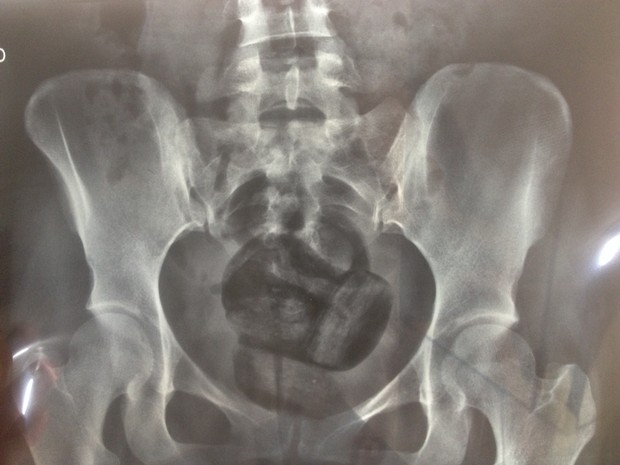

Imagem Ilustrativa